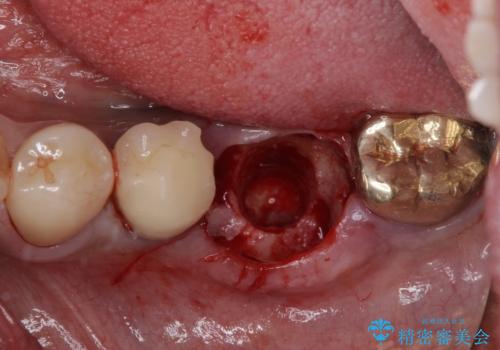

そのため、当院に新しく導入した手法により、抜歯をした日にインプラントを埋入し、そのままを仮歯を装着することで、他の歯への負担を軽減する計画を立てました。

インプラント埋入時に植立具合の安定性を測定したところ、十分な数値が得られたため、速やかに仮歯を装着して咬合回復をさせることができました。

抜歯を含めた外科処置を1回に抑えることができ、あっという間に治療を終えることができました。